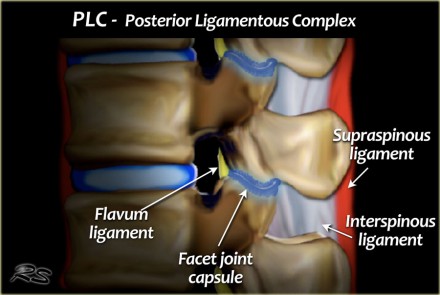

The PLC serves as a posterior "tension band" of the spinal column and plays an important role in the stability of the spine (3).

A torn PLC has a tendency not to heal and can lead to progressive kyphosis and collapse.

The PLC is composed of the supraspinous ligaments, interspinous ligaments, articular facet capsules, and ligamenta flava (figure).

The supraspinous ligament is a strong, cordlike ligament which connects the tips of the spinous processes from C7 to the sacrum.

The interspinous ligaments are weak, thin, membranous structures connecting the adjacent spinous processes.

The contractile force of the ligamenta flava presses the vertebrae together and keeps them aligned.

The facet joints act against rotational forces.